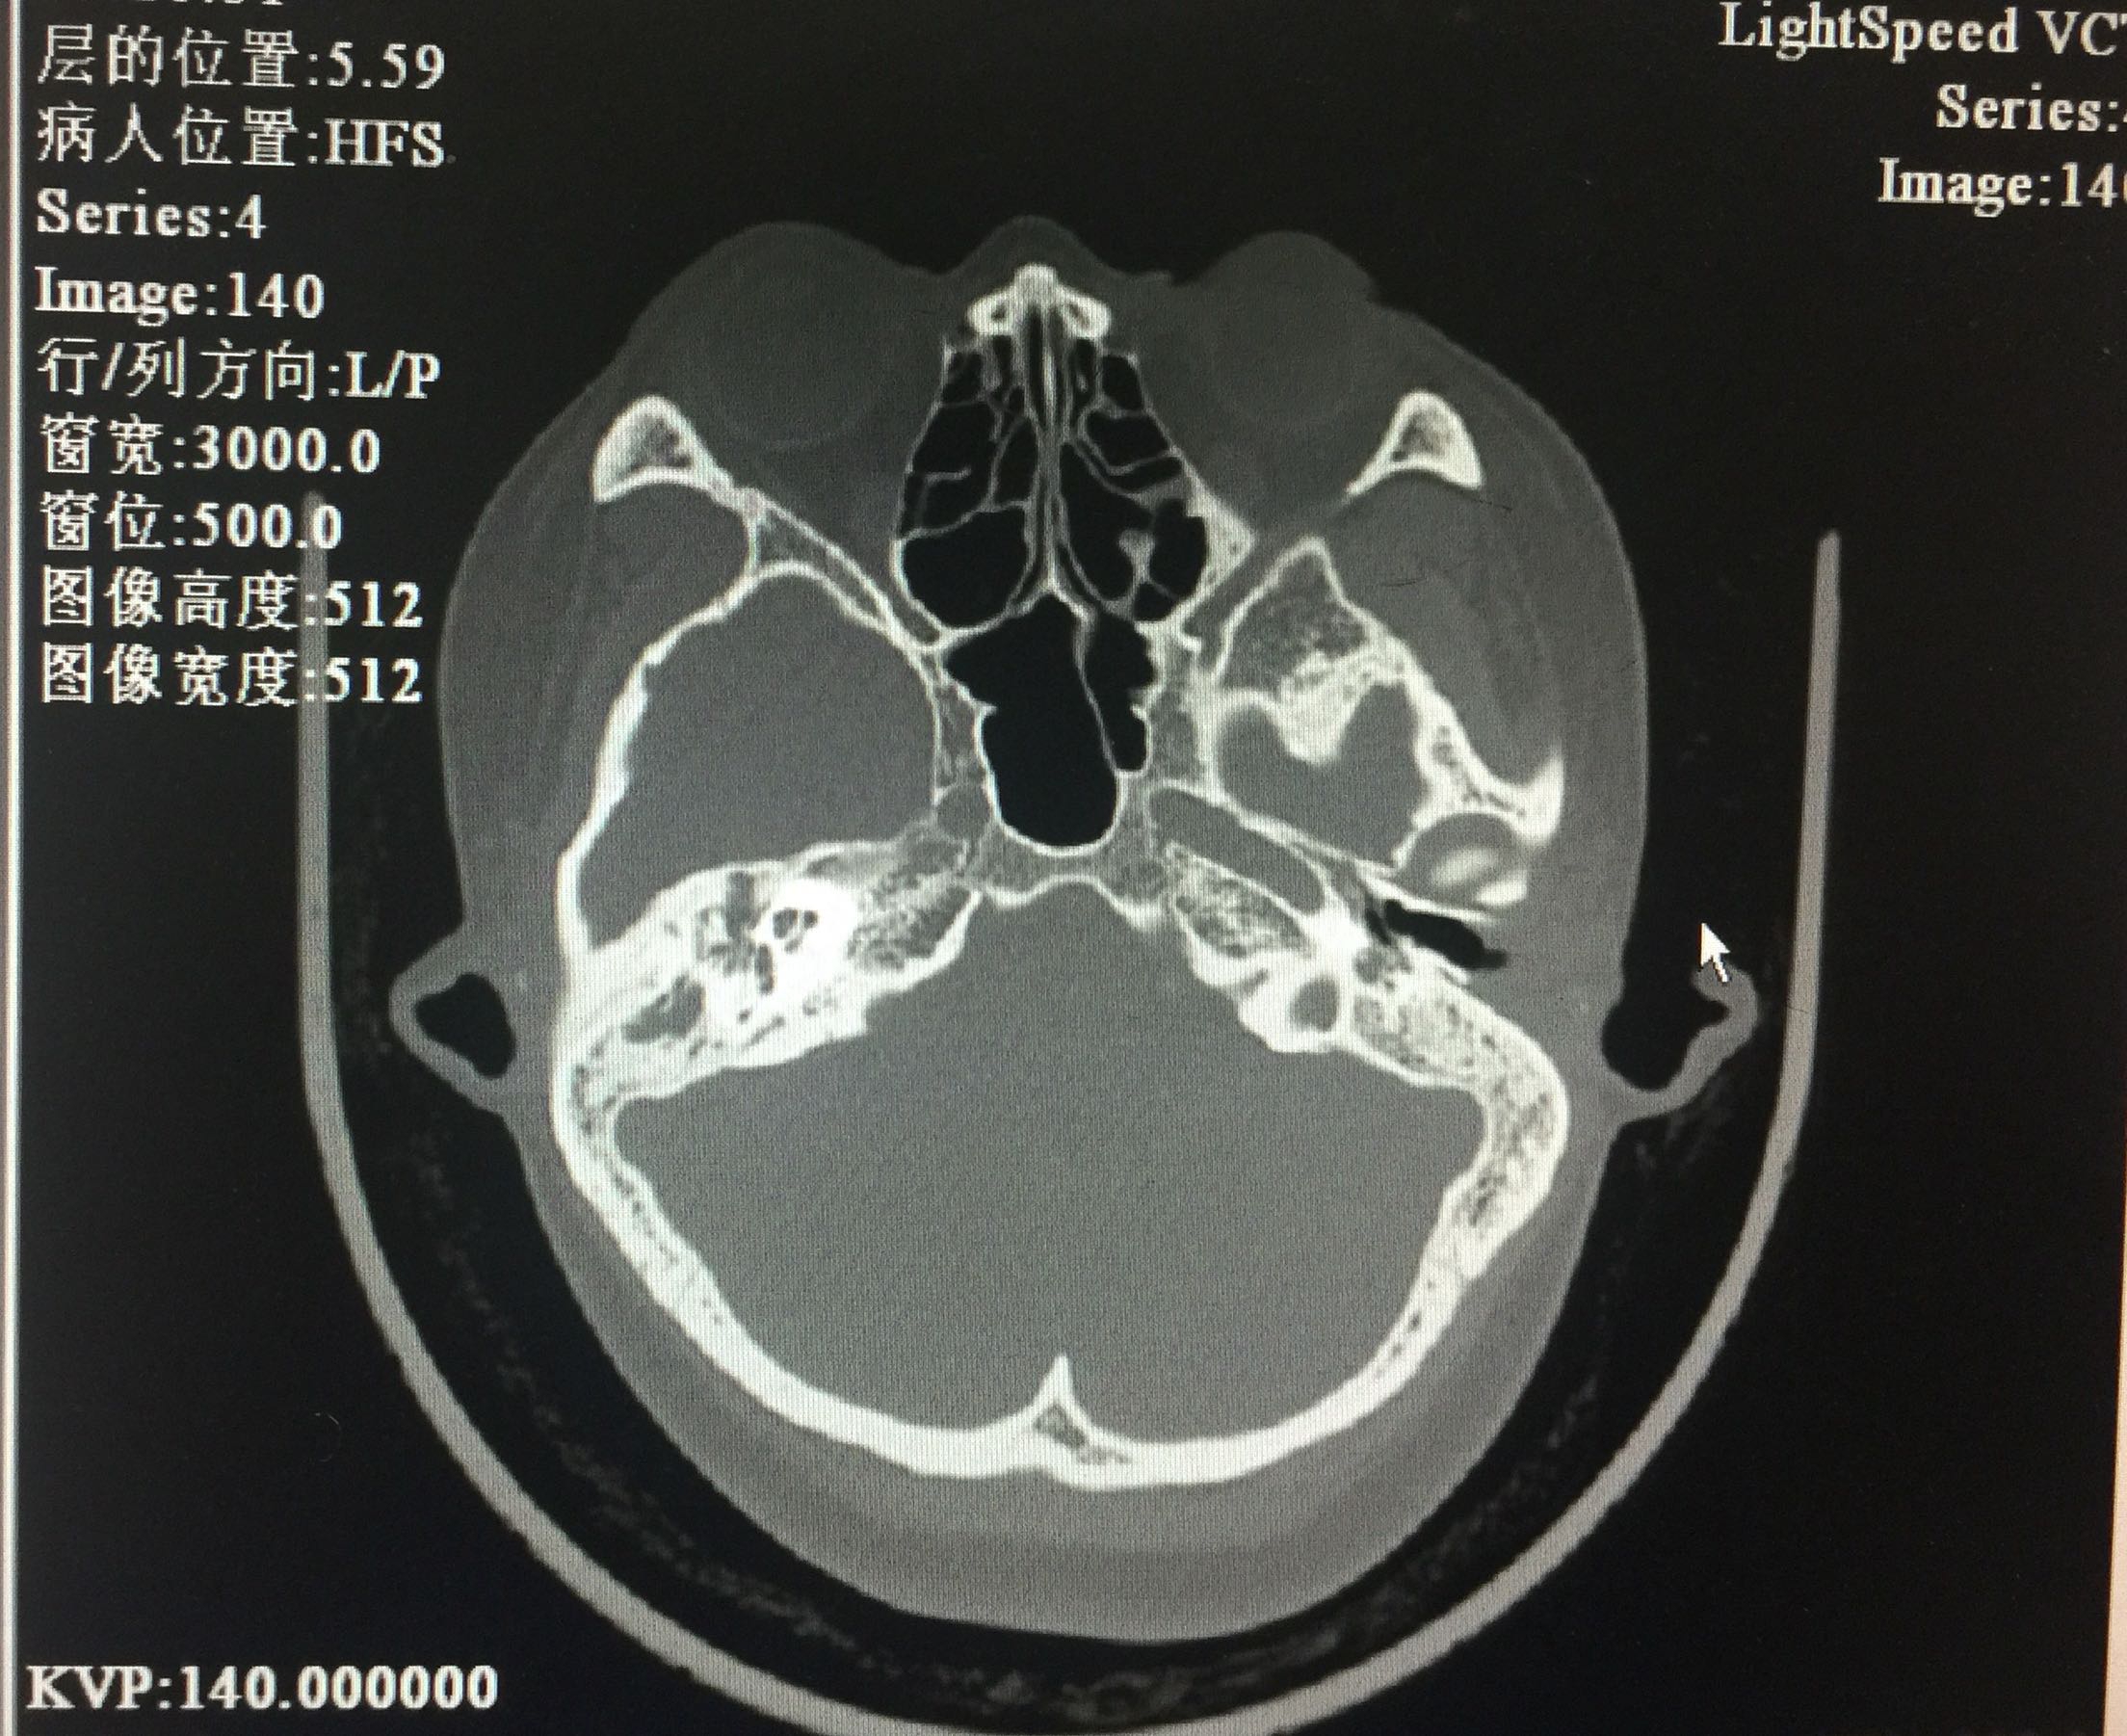

声导抗:双侧鼓室曲线B型,声反射未引出。颞骨CT:考虑双耳中耳乳突炎。

入院诊断:1.传导性聋(双)2.耳硬化症(双)?3.先天性小耳畸形(双)。治疗:入院后完善检查,全麻下行耳显微镜下左鼓室探查+骨岬开窗人工镫骨植入+外耳道成形术。左耳内切口,分离外耳道皮瓣见外耳道深部骨性狭窄,用电钻扩大外耳道,自后方完整掀开鼓膜后部。电钻磨开后鼓室,探查听骨链,见砧骨长突畸形变短,镫骨完全缺如,卵圆窗封闭,锤骨正常,锤砧关节活动好。用微钻圆窗后上相当于卵圆窗位置骨岬开窗,少量外淋巴液流出。选用合适人工听骨置于砧骨长脚上,末端植入骨岬开窗处。术后更正诊断为:1.传导性聋(双)2.先天性听骨链畸形(左)?3.先天性小耳畸形(双)。